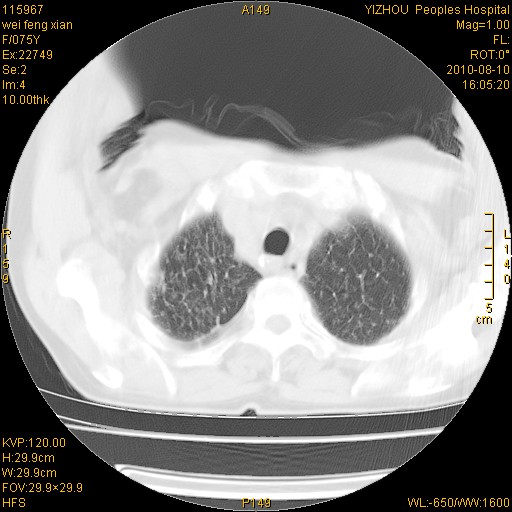

标题: CT28313:两肺弥漫性病变 [打印本页]

标题: CT28313:两肺弥漫性病变

女,75岁,患者反复头昏乏力面色苍白3年,再发10天入院。临床贫血查因。

双肺间质增生并右肺上叶炎性改变,不除外右肺上叶结核病肺内播散

考虑右肺上叶炎症合并双肺结核可能性大,建议上传纵隔窗ct图片。

双肺结核可能性大

考虑尘肺并结核;右上肺支气管扩张!

结核、尘肺、支气管肺泡癌都不能除外

右肺上叶继发性肺结核伴肺内血型播散!

考虑右肺上叶继发性肺结核伴两肺播散。